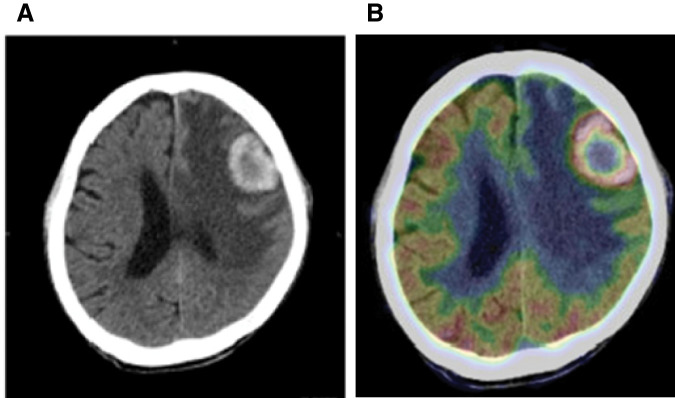

Case presentation: The patient was an 82-year-old man who visited a previous institution for anemia. Upper gastrointestinal endoscopy revealed a type 2 tumor extending from the esophagogastric junction to the upper part of the residual gastric body. Biopsy revealed tubular differentiated adenocarcinoma, and he was referred to our institution. He had a history of distal gastrectomy for a gastric ulcer in his 30s. After contrast-enhanced CT, we diagnosed residual gastric cancer (cT4aN + M0 cStage III). After three courses of preoperative chemotherapy with S-1 plus oxaliplatin, the patient underwent open total resection of the residual stomach, lower esophagectomy, D2 dissection, and Roux-en-Y reconstruction and was discharged without postoperative complications. Six months after surgery, thoracic and abdominal contrast-enhanced CT showed no apparent recurrence. However, 1 month later, he began to experience speech difficulties and mobility issues, and head CT revealed a 3-cm tumor in the left frontal lobe. After whole-body contrast-enhanced CT and PET-CT, the brain tumor was confirmed as a solitary lesion with no metastasis to other organs. The patient underwent open brain tumor resection, and pathology diagnosed brain metastasis from residual gastric cancer. Postoperatively, he underwent radiation therapy (40 Gy in 8 fractions) to the tumor cavity. At the time of writing, 24 months have passed since the gastrectomy and 16 months have passed since the removal of the brain tumor, with no significant neurological damage or other evidence of distant metastasis.